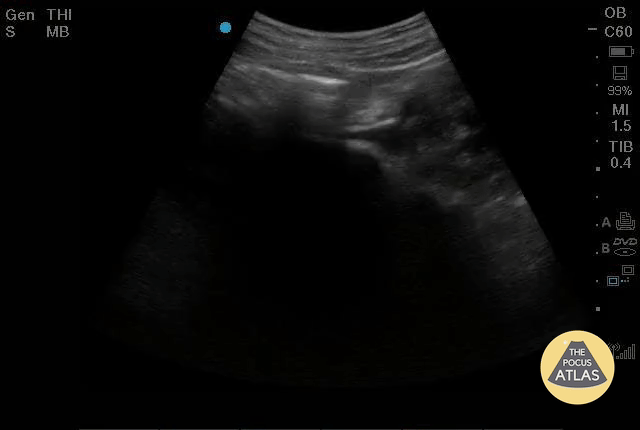

OB/Gyn - Bicornuate Uterus - Pregnant

“Bicornuate uterus” is not actually a dichotomous diagnosis - patients exist along a morphologic spectrum, and can actually get pregnant without much difficulty in some cases. Dr. Elias Jaffa, MD, MS, FACEP